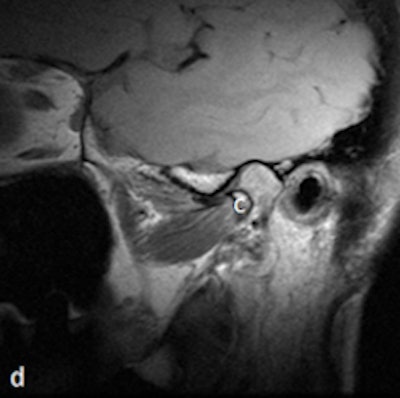

Dr. Friedman prefers that patients be supine on a stretcher with the jaw tilted away from the side to be examined. Then the person performing the ultrasound palpates the joint while the patient opens and closes her mouth. Gel is then placed on the joint, and the probe is placed at various positions around the joint. The images are examined to determine whether there is anterior displacement of the disk while the joint is the closed-mouth position.

"If the ultrasound is abnormal, the patient should be referred for an MRI, and any patient scheduled for surgery also must have an MRI," he said. "The main challenge is learning to detect what is normal on ultrasound. We also acknowledge that abnormal anteromedial and medially displaced disks may be missed or misinterpreted with ultrasound."